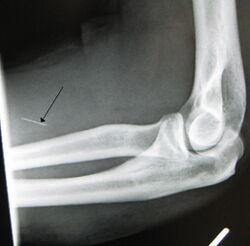

- Arterial damage – Arterial pseudoaneurysms may form at injection sites, which can rupture, potentially resulting in hemorrhage, distal ischemia, and gangrene. Inadvertent intra-arterial injection can also result in endarteritis and thrombosis, with ultimately similar consequences.[3]

The preferred injection site is the crook of the elbow (i.e., the Median cubital vein), on the user's non-writing hand. Other users opt to use the Basilic vein; while it may be easier to "hit", caution must be exercised as two nerves run parallel to the vein, increasing the chance of nerve damage, as well as the chance of an arterial "nick".[5]